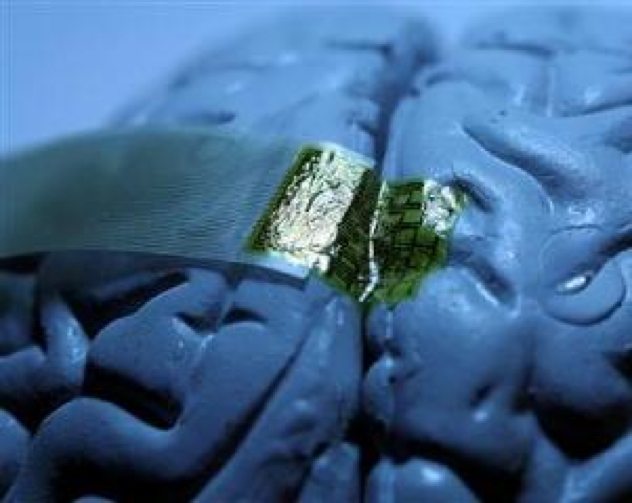

3. Cấy ghép thần kinh

Mô cấy ghép khá giống với công nghệ BCI nhưng thiết bị được gắn trực tiếp vào màng não để khắc phục hoàn toàn những tổn thương não, tăng và phục hồi chức năng nhận thức, phản xạ của não hoặc cung cấp một sức mạnh đặc biệt cho cơ thể như việc điều khiển máy móc từ xa...

Việc sử dụng cấy ghép thần kinh để kích thích sâu bộ não được phê duyệt bởi Cục quản lý thực và dược phẩm Hoa Kỳ để điều trị các chứng bệnh khác nhau từ năm 1997. Nó đã được chứng minh hiệu quả trong điều trị bệnh Parkinson và chứng loạn trương lực cơ, đau mãn tính và trầm cảm ở các mức độ khác nhau.